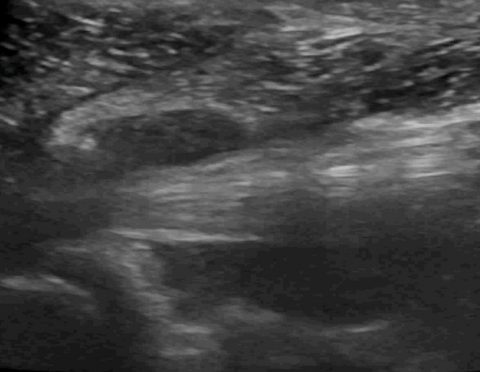

Sonography of canine mammary glands during lactation

Just a striking image of something not much depicted in the published literature. This is what normal, healthy lactating mammary gland looks like in the bitch (on this occasion two days post partum): &nbs… Continue reading